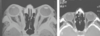

Dx

TC con engrosamiento muscular